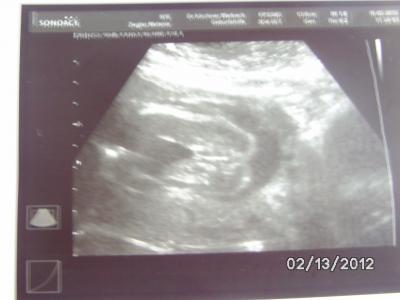

Hallo meine Lieben Hatte heute meine 2 VU und mit der kleinen ist alles in Ordnung sie sitzt Momentan in Beckenendlage (Seit 4Wochen schon) und ist 26cm groß und 500gramm schwer. Ich bin auch schon 3 Wochen weiter. Habe meinen FA gesagt er soll bitte nochmal nach dem Geschlecht schauen und es ist zu 100% eine Kleine Püppi,weit und breit keinen Bimpel zu sehen ich freue mich so. Heute habe ich noch einen 3D Termin ausgemacht den ich am 9.03. habe ich freue mich schon so darauf. Hier noch ein Outingbild von der kleinen... Liebe Grüße Melanie

Bild zu Wieder zurück von der VU freue mich so  (mit Bild) - Forum für Juni - Mamis